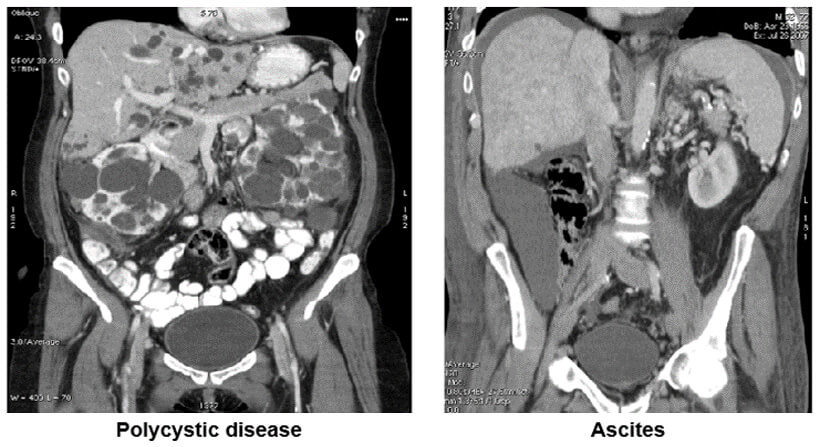

Images

In the image on the left, we see the polycystic disease of both kidneys while the image on the left shows the presence of ascites in the abdomen.